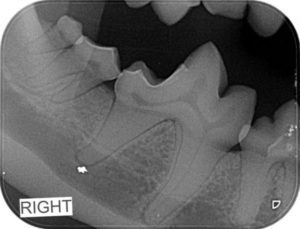

Then your pet is not alone. 80% of pets that we see do need some dental attention. The good news is that a Scale, Polish & Assessment (or SPA) is a routine procedure and we do them every day, so our vets and nurses are really experienced. Part of your pets SPA Procedure will involve dental X-rays which are essential for us to fully assess what is happening in your pet’s mouth. The dental X-rays above belong to Gus, who is a Miniature Schnauzer. Gus came in for a Healthy Pets 4 Life check-up and dental and although his mouth appears normal to the eye, the X-rays revealed disease below the gum line that needed our attention; luckily we caught it on the X-rays. It was after treating Gus that we began to include dental X-rays in our routine dental procedures so we didn’t miss any more sore teeth that needed treating.

This picture show disease under the gum line that we couldn’t see or find with dental probing